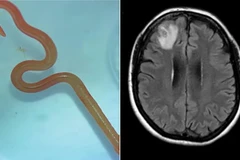

Các nhà nghiên cứu cho rằng người phụ nữ này bị nhiễm bệnh sau khi chạm hoặc ăn phải những loài rau gần nhà được cho đã nhiễm trứng giun thải ra từ chất bài tiết của một con trăn.